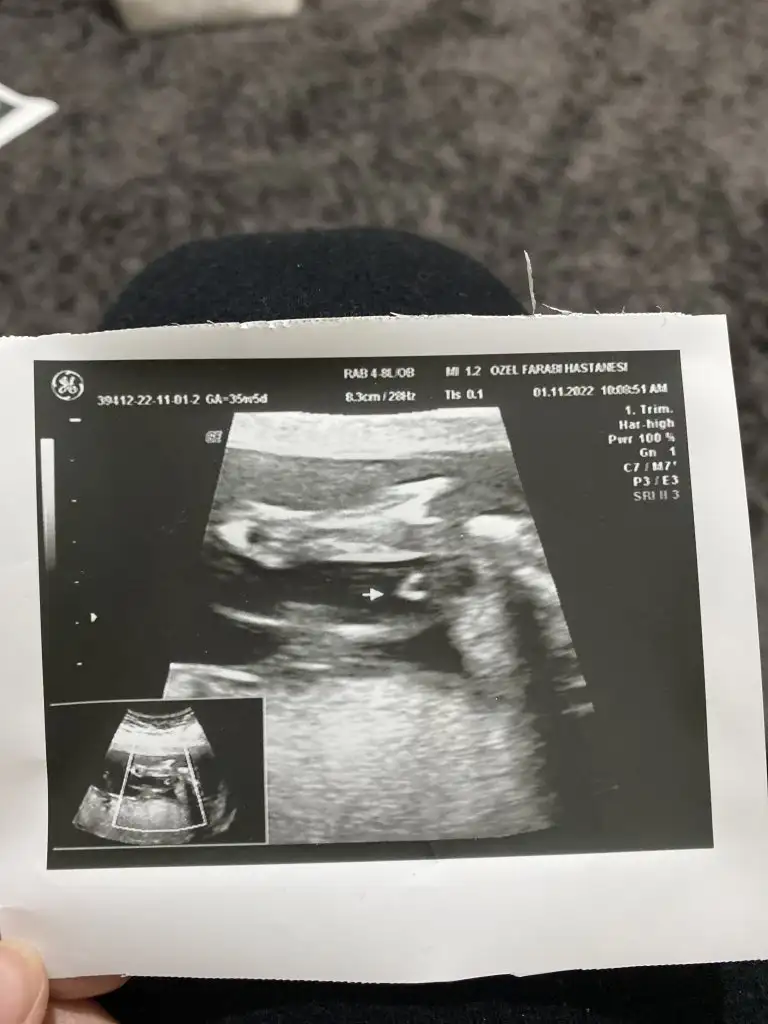

Ultrason fotoğrafına bakar misiniz lütfen

Doktorum bu görüntüye rağmen %100 erkek diyemem dedi ama elimize görüntüyü dahi verdi 10 gün sonra detaylı ultrason zamanım geliyor %100 o zaman diyecekmiş..bizce cok net erkek size de sormak istedim

Nedense içime kız gübi doğdu..bişey anladığımdan değil

Fotonun tekinde kiz gbi duruyo ama ok isaretli yer pipiyse eger erkek tam cikaramadim bende